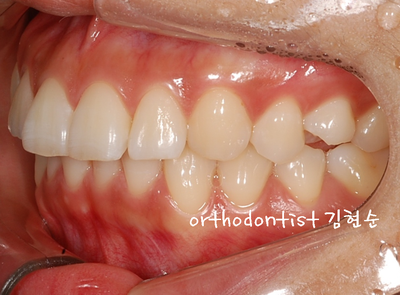

세라믹 치과 오시는 길 - 돌출 교정 - 교정 문의 환자 : 김 0 0 나이 : 24 세 F 교정 사유 : 치아 돌출 / 턱관절 호소 앞면 비대칭이 보입니다 웃을 때도 약간 삐뚤어 보입니다 입도 돌출된 모습을 확인할 수 있습니다 mi...

교정 문의 환자 : 김 0 0

나이 : 24 세 F

교정 사유 : 치아 돌출 / 턱관절 호소